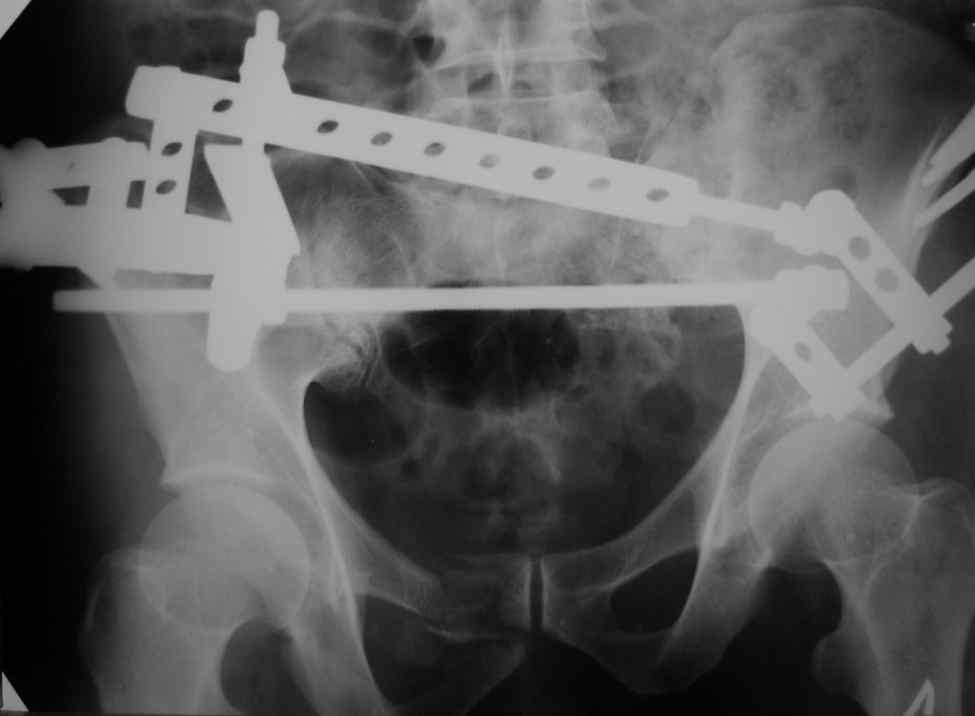

Отправитель: Владимир Бахарев 16 Ноябрь 2006, 12:13

Снимки вот

Можно посмотреть на нынешние снимки таза в аппарате, фас и inlet?